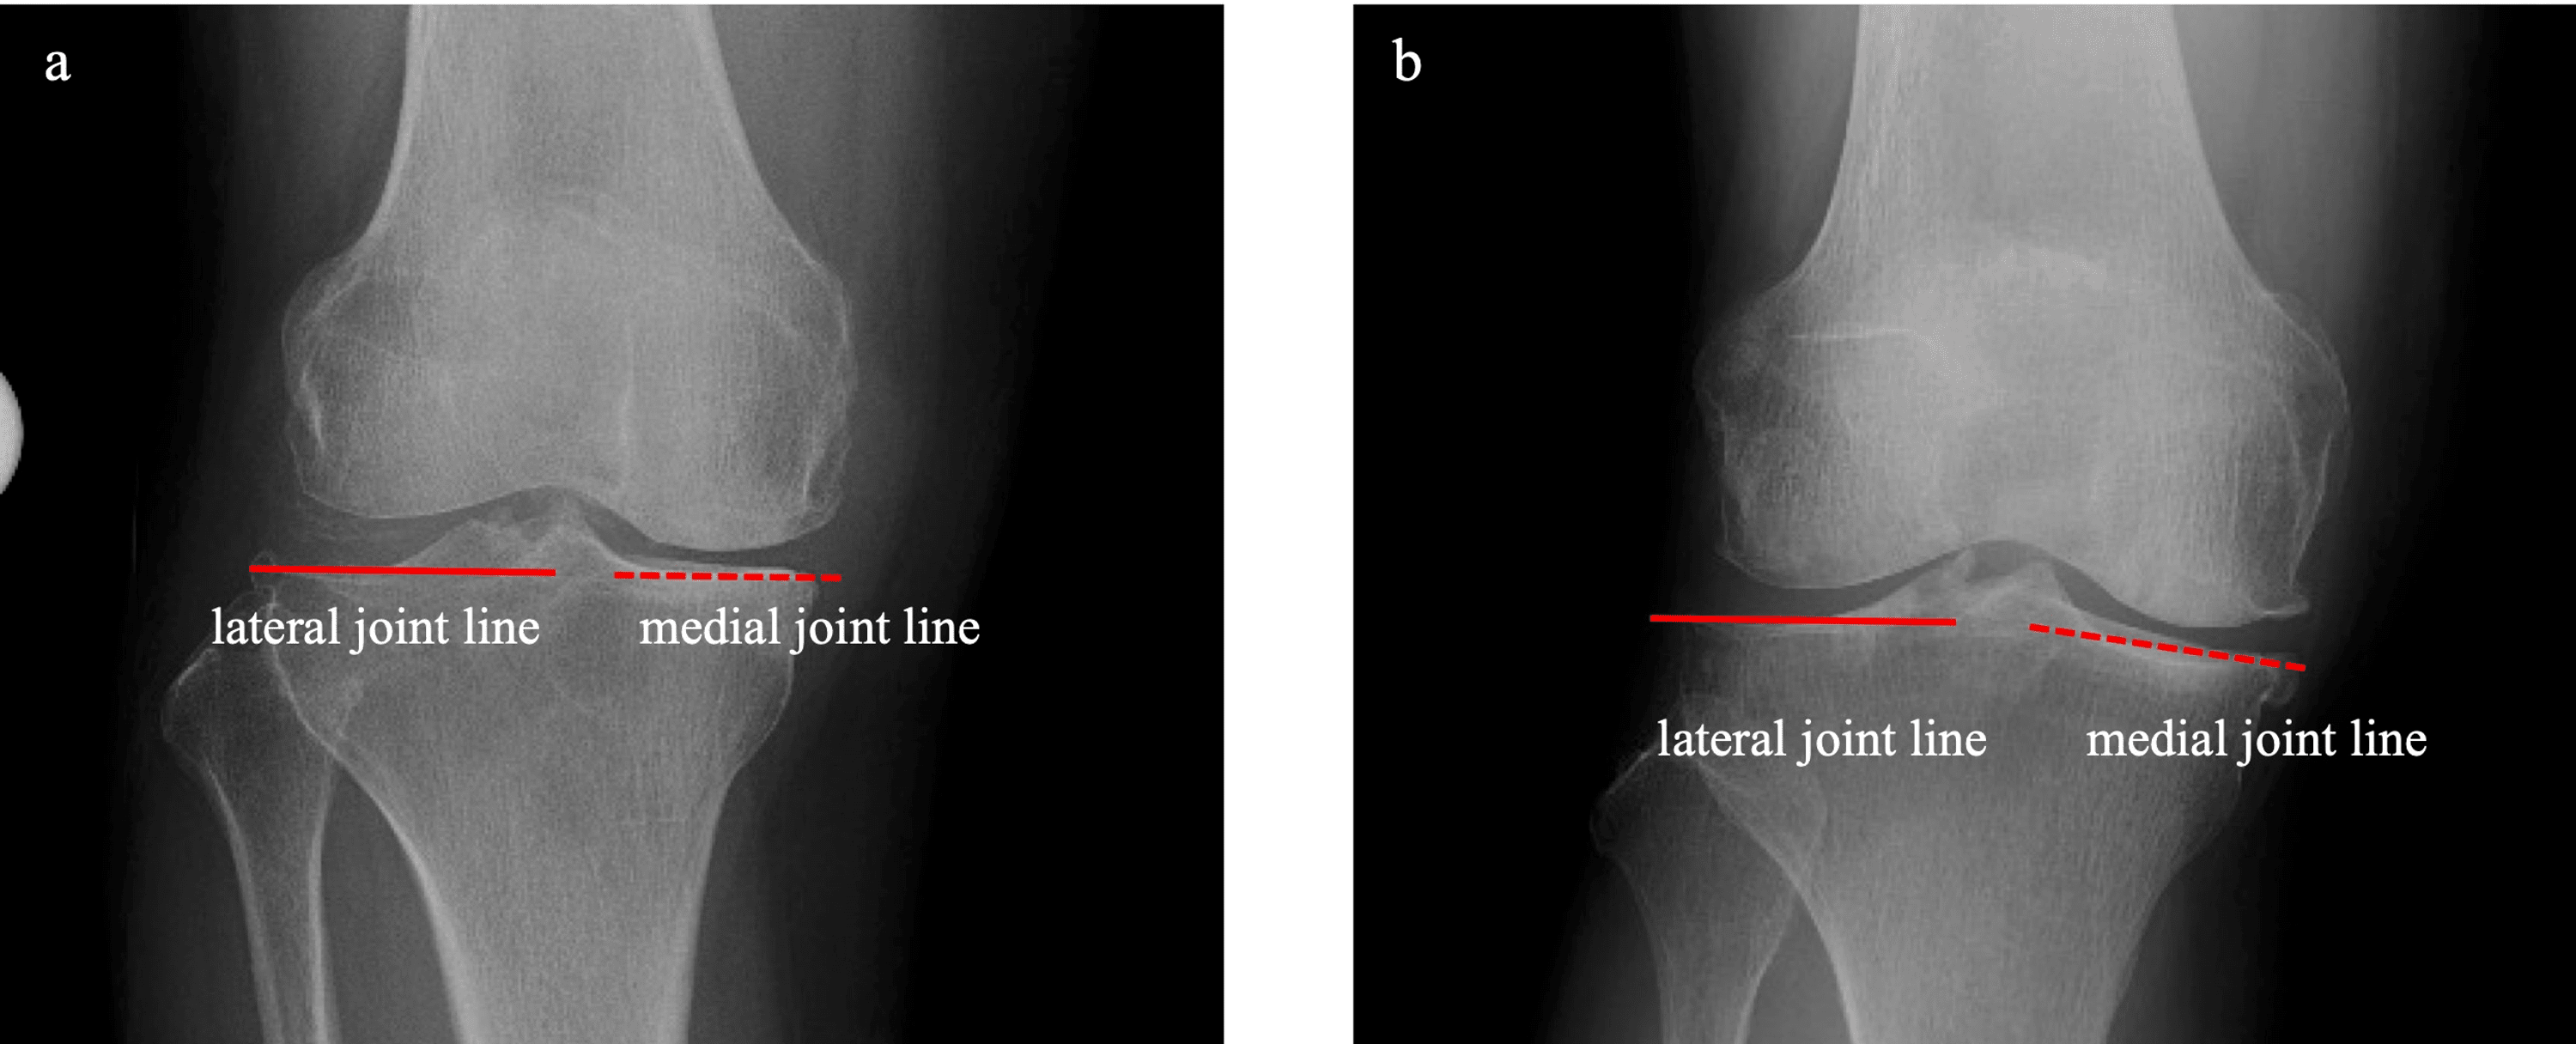

2 Composite shows that the kinematically aligned TKA ( left patient What Is Kinematic Knee Alignment — kinematic alignment (ka) is an alternative philosophy for aligning a total knee replacement (tkr) which aims to. kinematically aligned tka, provides an overview of the sur gical technique of kinematic alignment with patientspecific. — kinematic alignment (ka) is an alternative philosophy for aligning a total. — kinematic implantation of tka can be done reliably at. What Is Kinematic Knee Alignment.